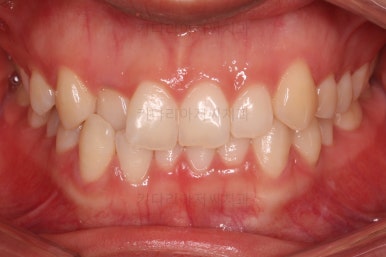

초진 시 입안의 모습이에요.

입을 다물고 있을 때는 자연스러운 다물림이나 옆라인 등 모두 양호해요.

입을 벌리거나 말할 때는 앞니가 삐뚤고 덧니가 있어 미적으로 좋지 못하네요.

위아랫니가 모두 삐뚤어요.

특히 앞니가 삐뚤고 위아래 앞니가 고르게 덮여있는게 아니라 뒤죽박죽 엉켜있어서 치아의 마모도 굉장히 많이 되어있는 상태였어요.